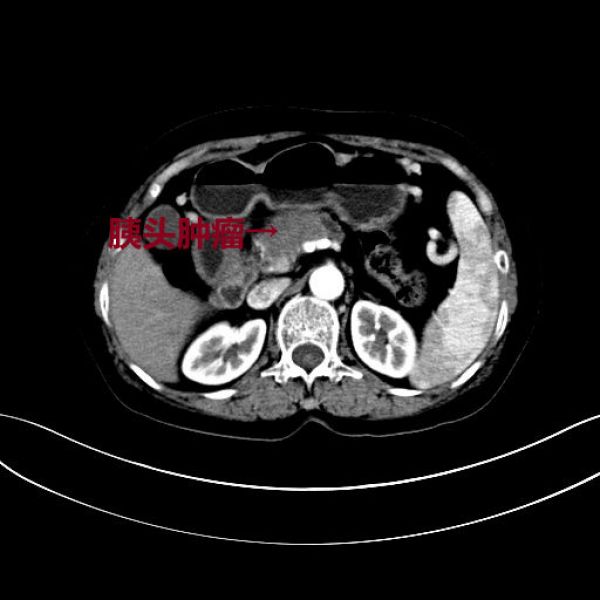

病人彭某某,61岁,因“体检发现胰腺占位1周”入住肝胆外科一病区,完善CT、MRI等影像学检查后,入院诊断为:胰颈部肿块,考虑胰腺癌,且周围血管侵犯可能性大。经科内讨论,认为患者胰腺颈部肿瘤局限,没有远处转移,一般情况良好,有手术指征和手术条件,加上患者及家属手术意愿强烈,可以实施手术。但该胰颈部肿瘤较大,最大径为5cm(T3期以上),该部位肿瘤常常累及背侧和头侧的血管,如背侧的肠系膜上静脉、脾静脉、门静脉,头侧的肝总动脉、腹腔动脉、脾动脉;一旦术中确认血管侵犯,为实现肿瘤的R0切除,则可能需要进行血管切除重建。在胰腺的切除范围上,有全胰腺切除和扩大的胰头十二指肠切除两种术式选择,全胰切除术后,胰腺的内、外分泌功能完全丧失,势必影响患者的生活质量,但是,决定是否能保留远端部分胰腺,还是取决于术中胰腺断端是否获得阴性切缘;患者的手术难度非常大,且术前带有诸多不确定性!

术前CT

术后复查CT